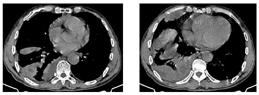

胸部CT(图2、图3):右肺下叶团块状影伴液化坏死,考虑感染(肺脓肿可能),不除外肿瘤;双肺下叶散在感染灶;右侧胸膜增厚,右侧胸腔积液,部分包裹;纵隔淋巴结肿大。床旁心电图:窦性心律,正常心电图。红细胞沉降率82 mm/h;血常规:白细胞计数22.66×109/L,中性粒细胞绝对值19.66×109/L,淋巴细胞绝对值0.72×109/L,嗜酸细胞绝对值0×109/L,血红蛋白121 g/L,中性粒细胞百分率86.8%;C反应蛋白343.78 mg/L;肝功能:谷丙转氨酶19 U/L,谷草转氨酶36 U/L,白蛋白38.7 g/L,前白蛋白93 mg/L,间接胆红素18.6 umol/L,直接胆红素13.7 umol/L,总胆红素32.3 umol/L;肾功能正常;血钠133.3 mmol/L;随机血糖7.87 mmol/L;凝血功能:纤维蛋白原降解产物5.5 μg/ml,血浆纤维蛋白原8.8 g/L,D-二聚体0.97 mg/L;血气分析(吸氧2 L/min):酸碱度7.47,氧分压81 mmHg,二氧化碳分压39.3 mmHg,剩余碱4.1 mmol/L,氧饱和度96.6%;降钙素原2.65 ng/ml;心肌梗死标志物、N-末端脑钠肽前体、肺肿瘤标志物、感染性疾病筛查未见异常;2019新型冠状病毒核酸阴性;常见呼吸道病原体抗体阴性;G试验阴性;痰涂片查结核、真菌阴性;痰、血培养阴性。

初步诊断:右下肺脓肿,右侧包裹性胸腔积液,支气管哮喘。给予头孢哌酮舒巴坦(3 g,1次/12h)静脉滴注抗感染,同时予吸氧、解痉平喘、止咳祛痰、补液、营养支持等对症治疗。为除外肿瘤和结核,于11月1日行支气管镜检查,见右肺下叶段支气管黏膜充血肿胀,可见散在黄褐色黏痰;在右肺上叶前段、右肺下叶行支气管肺泡灌洗。肺泡灌洗液涂片:上皮细胞≤10/LP、白细胞≥25/LP,G+杆菌1+,G—杆菌1+,查见少量G—双球菌,结核分枝杆菌复合群阴性,未查见抗酸杆菌和真菌。肺泡灌洗液培养:铜绿假单胞菌,对头孢哌酮舒巴坦敏感。复查红细胞沉降率94 mm/h;血常规:白细胞计数22.41×109/L,中性粒细胞绝对值19.07×109/L,淋巴细胞绝对值0.84×109/L,血红蛋白109 g/L,中性粒细胞百分率85.1%;C反应蛋白360.21 mg/L;降钙素原1.25 ng/ml。患者痰量较前增加,呈腥臭味,血液炎症指标仍高,联用克林霉素(0.6g,1次/8h)静脉滴注以覆盖厌氧菌,并再次送检痰培养,仍呈阴性。完善胸部彩超检查示:左侧胸腔肋膈角探及间距约1.3 cm无回声区,右侧胸腔探及范围约5.8 cm×10.8 cm液性暗区反射,其内可见蜂窝状稍强回声分隔,透声差;另于穿刺点处探及范围约6.6 cm×2.9 cm液性暗区反射,进针深度约2.8 cm;右肺组织内探及多处液性暗区反射,其内透声差,可见絮状低回声漂浮,较大范围约7.9 cm×4.9 cm;提示双侧胸腔积液(右侧包裹性),右肺超声所见考虑肺脓肿。因进针深度不够,床旁胸腔穿刺失败。于11月2日在超声引导下行胸腔穿刺术,胸水常规:深黄色、浑浊胸水,无凝块,白细胞总数45660 ×106/L,单个核细胞25%,多个核细胞75%,红细胞30×109/L,李凡他实验+++;胸水生化:白蛋白29.6 g/L,球蛋白25.6 g/L,总蛋白55.2 g/L,淀粉酶30 U/L,葡萄糖0.31 mmol/L,乳酸脱氢酶2427 U/L,腺苷脱氨酶72 U/L;胸水培养(需氧菌+厌氧菌)阴性。胸水检验结果支持脓胸。胸部增强CT(图4,图5,图6):右肺下叶团块状影,考虑肺脓肿,伴脓胸形成,建议治疗后复查除外肿瘤;双肺下叶散在感染灶,较前加重;右侧胸膜增厚,右侧胸腔积液,部分包裹;纵隔淋巴结肿大。